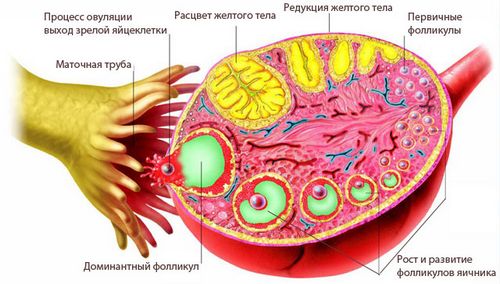

Другий тиждень вагітності відноситься до так званої фолікулярної фазі менструального циклу. В кінці її домінантний фолікул перетворюється в зрілу яйцеклітину і залишає яєчник - так відбувається овуляція.

Відбувається це так: бульбашка фолікула досягає діаметра близько 2 см, потім його ріст припиняється і всередині наростає тиск рідини. Потім під впливом лютеїнізуючого гормону він лопається і назовні виходить зріла гамета, готова до зустрічі зі сперматозоїдом. В середньому вона живе 24 години, за цей час і відбувається запліднення. Тому в більшості випадків дата зачаття збігається з овуляцією.